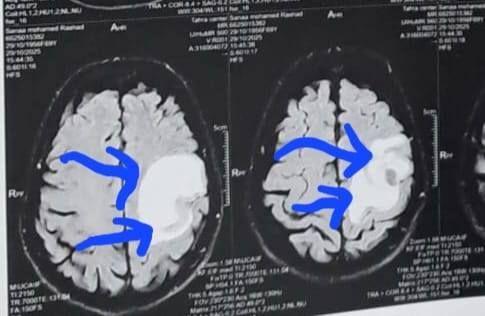

وكشف الدكتور إبراهيم الغريب رئيس قسم جراحة المخ والأعصاب بالمستشفى، أنه تعود تفاصيل الحالة إلى استقبال المستشفى المريضة بالعيادة الخارجية وهي تشكو من تنميل وضعف بالجانب الأيمن وثقل بسيط في الكلام، وبإجراء الفحوصات اللازمة من أشعة مقطعية ورنين مغناطيسي بالصبغة، تبين وجود ورم بالمخ، وتم إعطاؤها العلاج المناسب لحين استكمال الفحوصات.

أشعة المريضة

الأشعة الخاصة بالمريضة

الأشعة